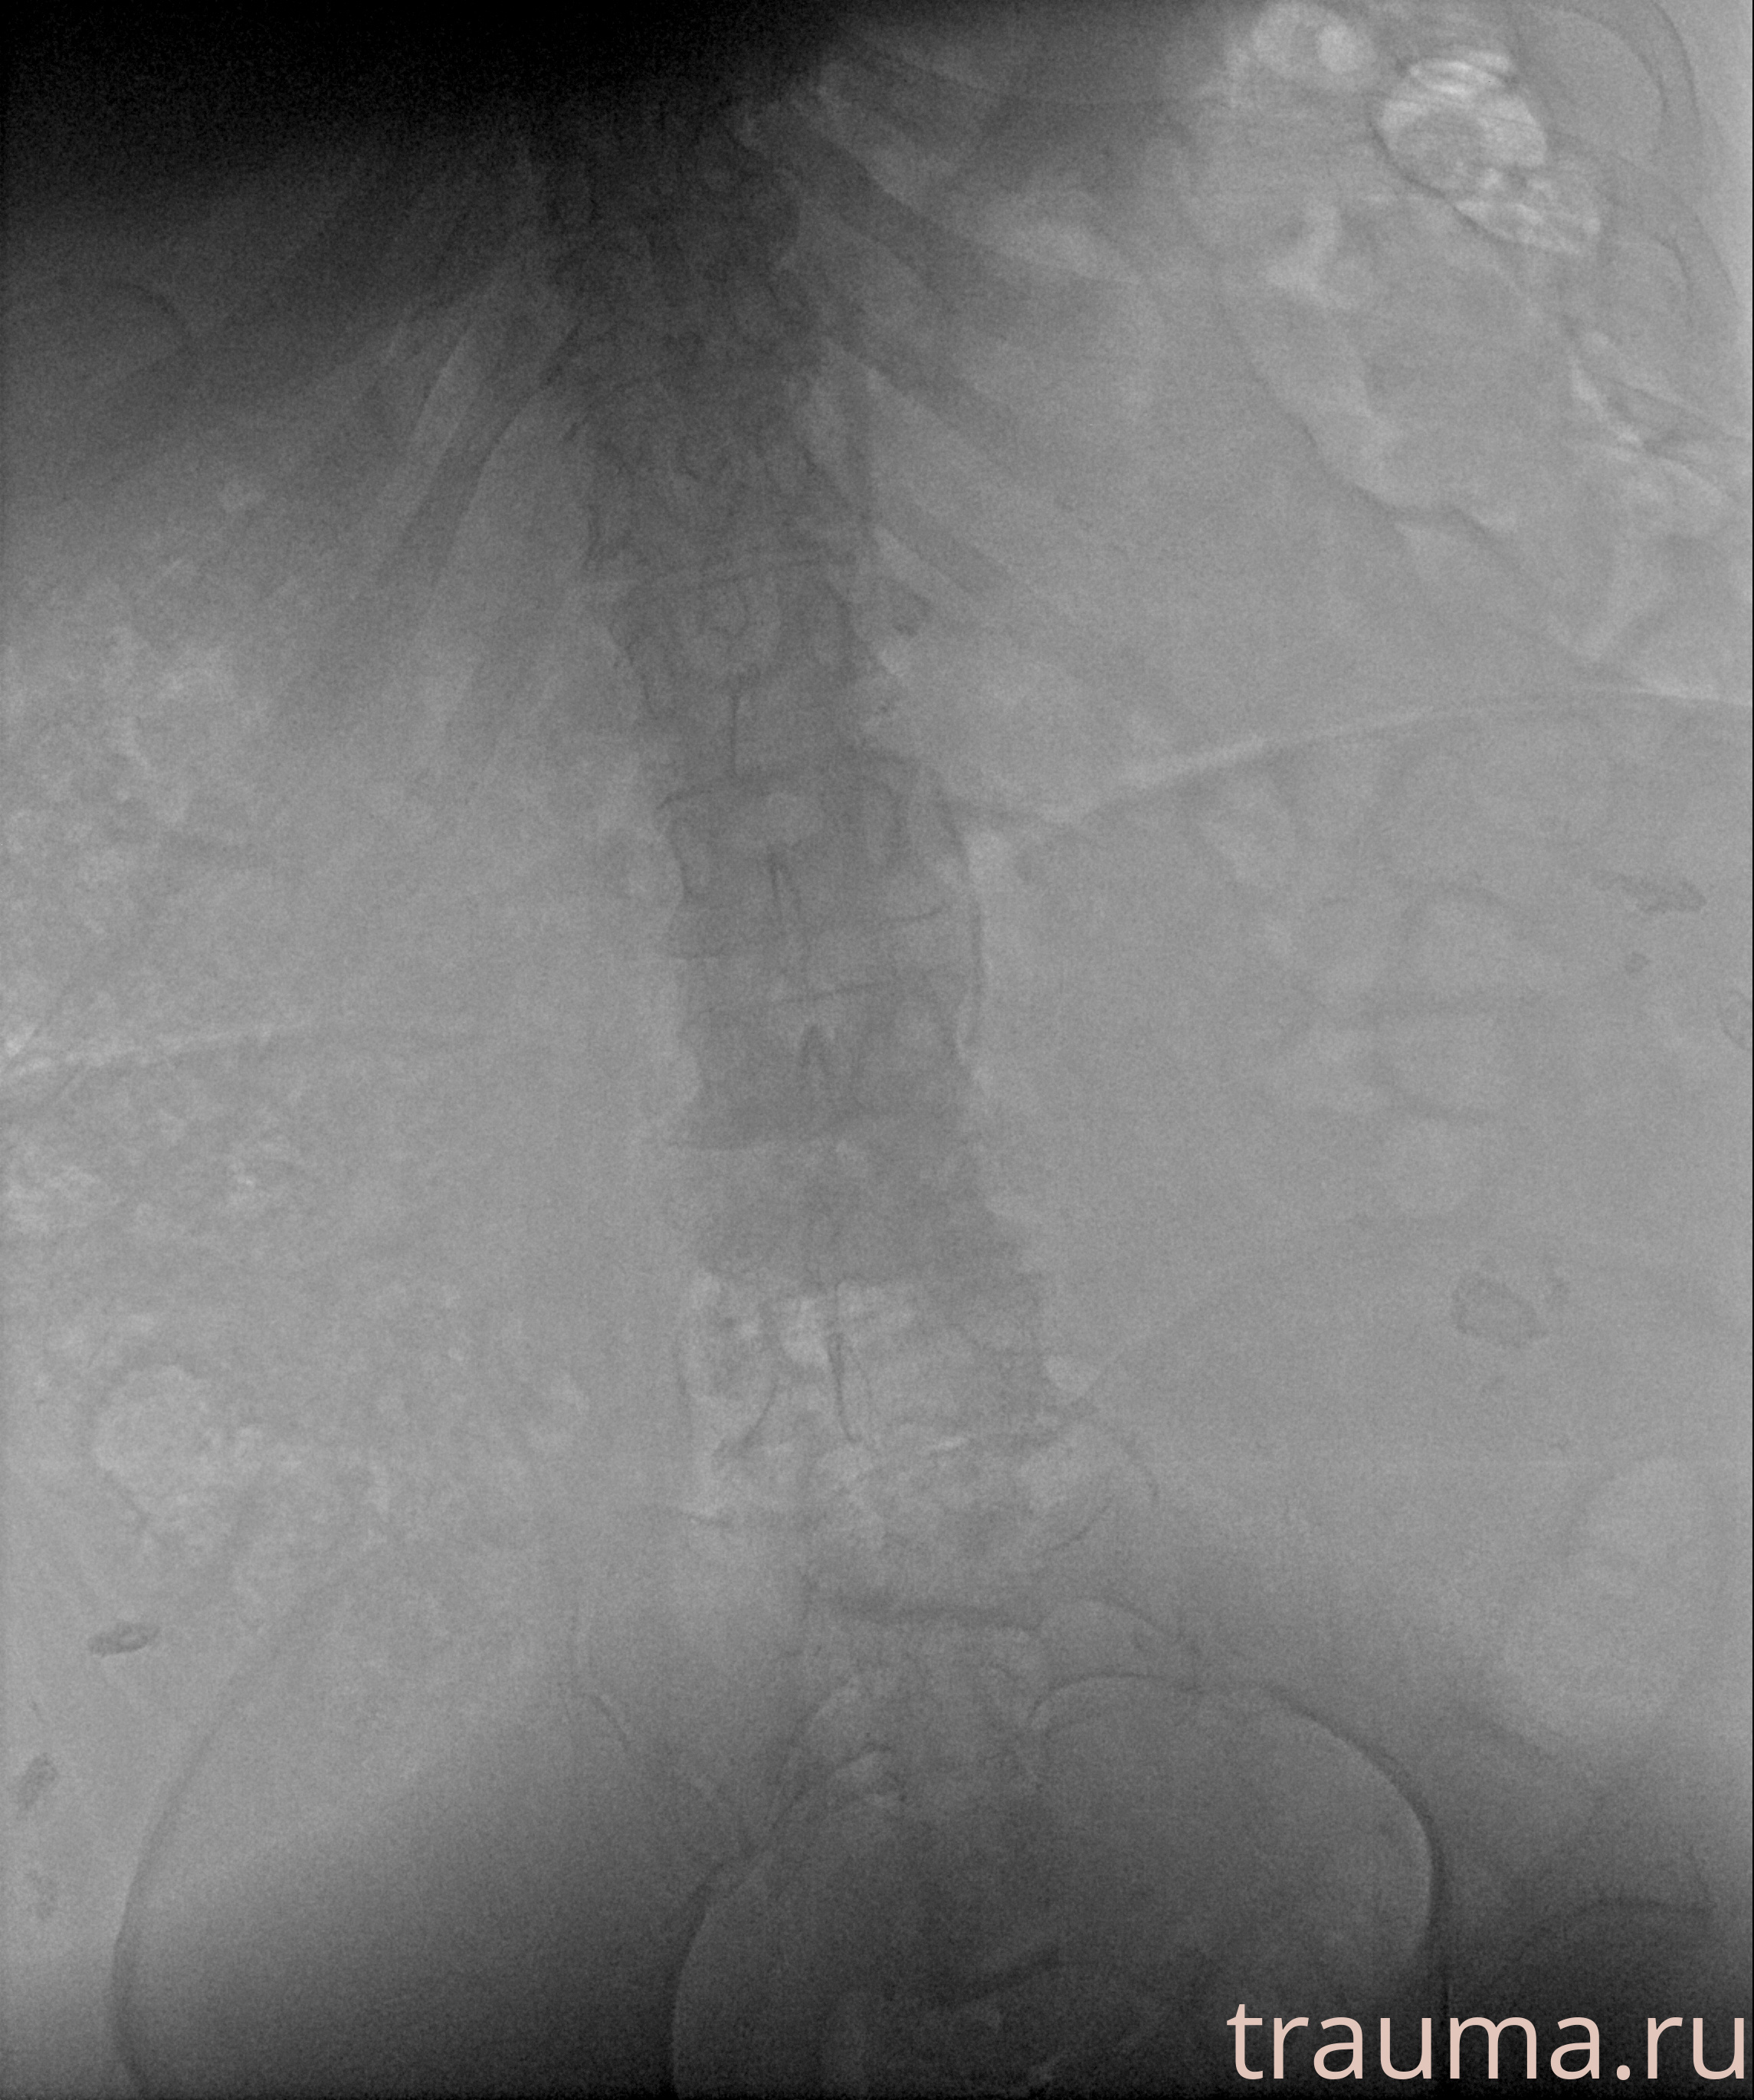

Рентгенограммы

Рентген на дому: по вашему адресу приезжает врач-рентгенолог, травматолог-ортопед с мобильным рентгеновским аппаратом, проводит диагностику травмы или заболевания, делает необходимые рентгенограммы, дает рекомендации по дальнейшему лечению. Получить качественные снимки в домашних условиях возможно благодаря уникальной методике, разработанной МосРентген Центром для института  Склифосовского